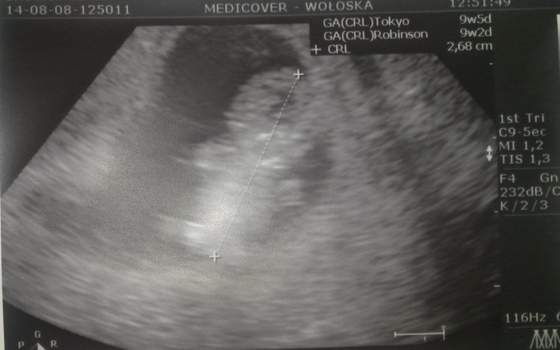

Wiesz Heven, a mi się tak jakoś wydaje, że znów syna będę miała... Ciekawe, czy się sprawdzi...